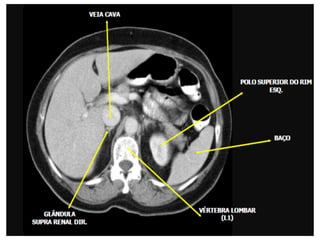

Imagem de corte axial com

janela para tecido ósseo

Tomografia do Abdome